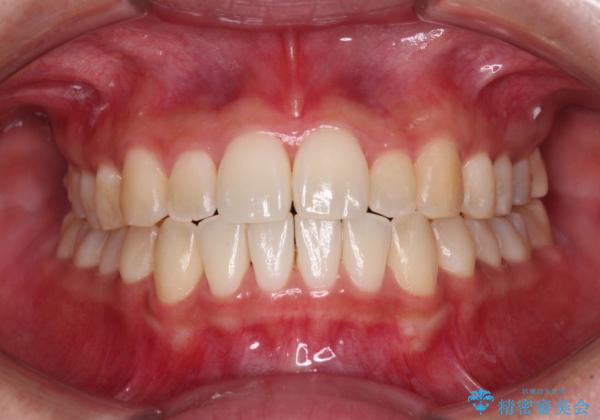

すきっ歯とオープンバイトをインビザラインで改善

- 前歯の上下スペースと前歯の隙間を気にして来院された患者様です。

インビザラインにより上下の前歯の隙間を閉じていくこととしました。

上下の隙間に舌が入り込むことが、すきっ歯やオープンバイトの原因であったため、舌の筋肉のトレーニングも並行して行い、後戻りの抑制を図りました。